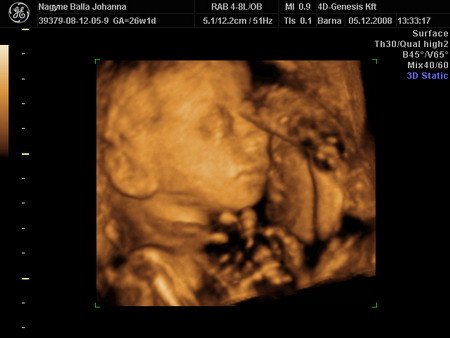

Lukács mindenkinek köszöni a dicséreteket! Én is.

Trinky! Igen, most kezd hízni Lukács. Én is... (61 kiló) Nagyon gyorsan nő a hasim. Mértem, centivel. 1,5 centi egy hét alatt. Sokat mozog, rúg nagyokat. Volt, hogy szinte feljajdultam. De ez nem panasz.

Kicsibé! Köszike! Bár én most inkább azt mondom, tiszta apja. De olyan mindegy ugye? Csak egészséges legyen, meg végre van.